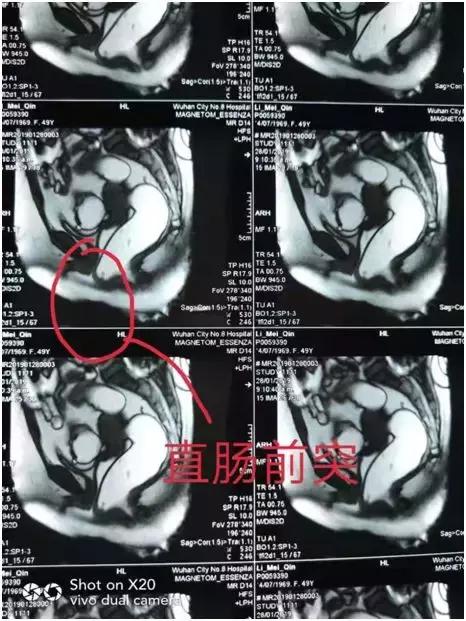

2月23日,光山县人民医院普外科陆永广团队在河南中医药大学第一附属医院肛肠诊疗中心张向安主任的指导下,成功对一位出口梗阻性便秘的患者行外科手术治疗,并诊断出口梗阻性便秘是由于直肠前突及耻骨直肠肌肥厚造成,遂采取经肛直肠前突修补术+耻骨直肠肌松解挂线器挂线术+直肠粘膜硬化剂注射术,手术取得了不错的效果。

该手术作为出口梗阻性便秘的经典手术方式,术后症状改善率90%以上,复发率较低!病人非常受益。这还是在我院首次引用治疗出口梗阻性便秘,临床中很多便秘的病人都用泻药作为治疗便秘的唯一选择,普外科陆永广主任再次提醒大家,出口梗阻性便秘主要是指排便出口附近组织、器官的改变,导致排便困难或羁留性便秘,大便堵塞肛门,多数病人靠开塞露,灌肠,甚至有的需要用手指协助排除,导致病人多数苦不堪言,长期受罪!建议大家应多咨询专科医生。